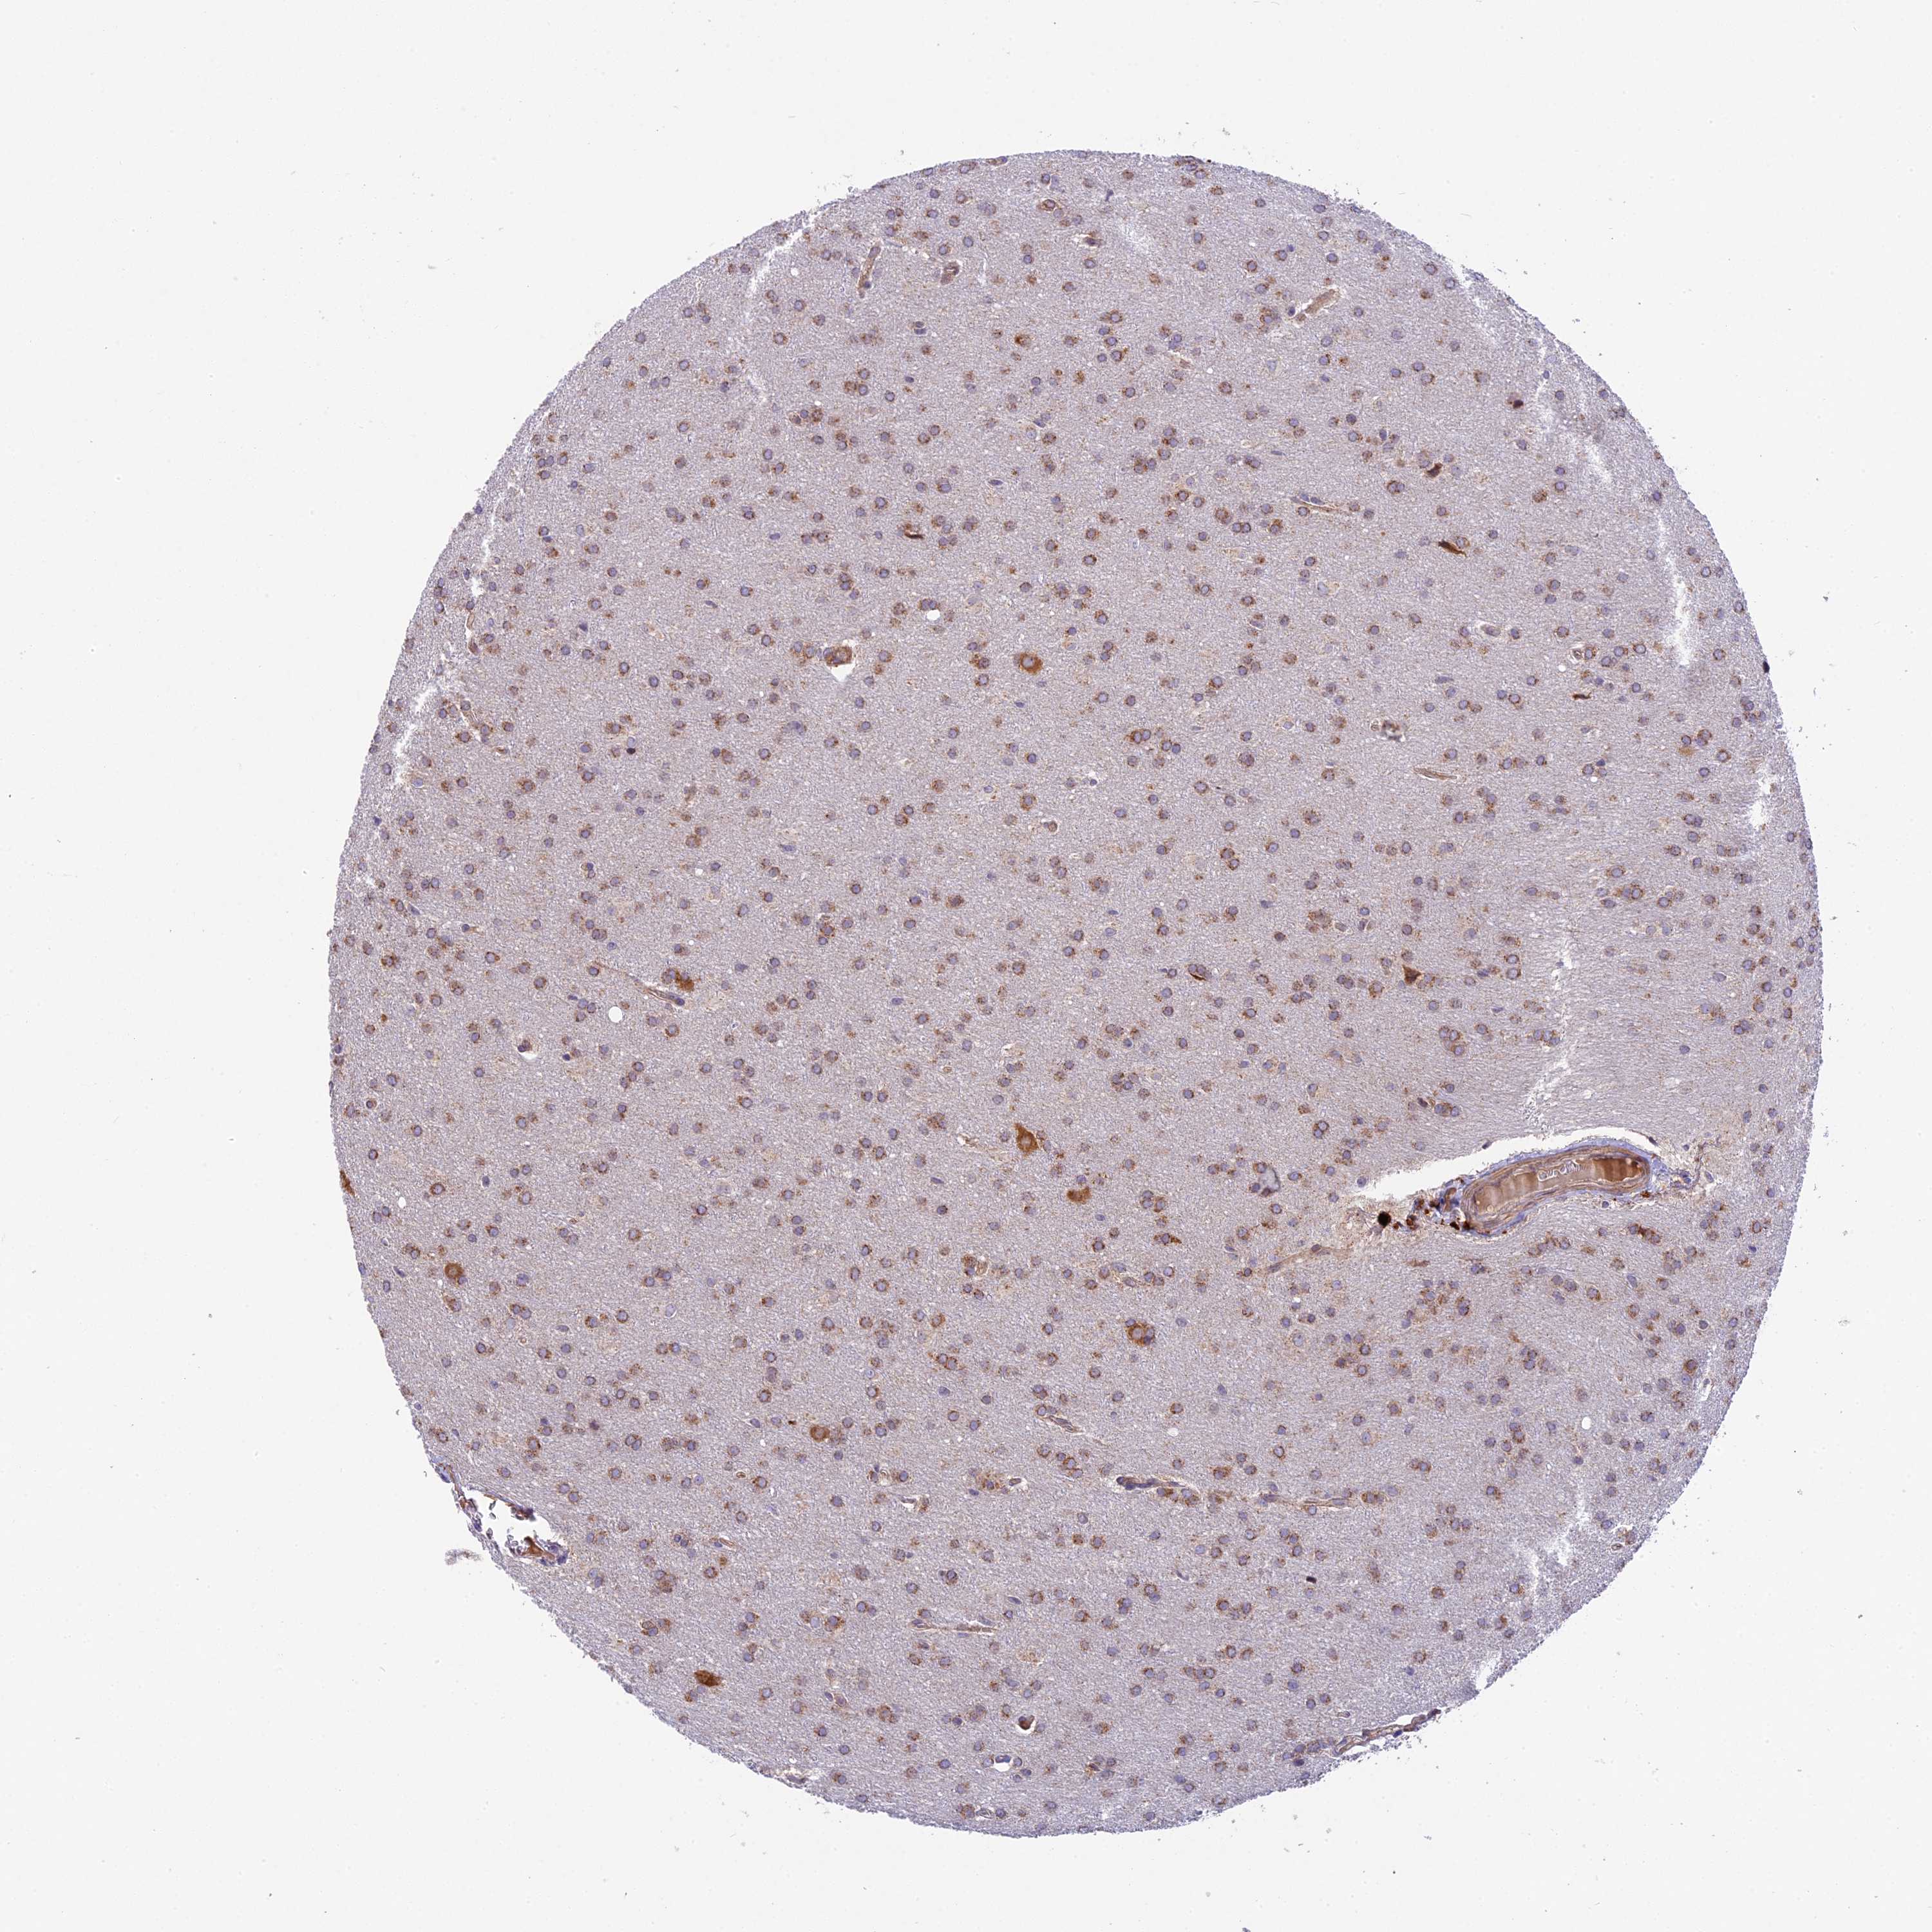

GLIOMA - Protein expressioni

A mouse-over function shows sample information and annotation data. Click on an image to view it in a full screen mode. Samples can be filtered based on level of antibody staining by selecting one or several of the following categories: high, medium, low and not detected. The assay and annotation is described here.

Note that samples used for immunohistochemistry by the Human Protein Atlas do not correspond to samples in the TCGA dataset.

Antibody stainingi

Antibody staining in the annotated cell types in the current human tissue is reported as not detected, low, medium, or high, based on conventional immunohistochemistry profiling in selected tissues. This score is based on the combination of the staining intensity and fraction of stained cells.

Each image is clickable and will lead to virtual microscopy that enables deeper exploration of all samples and also displays staining intensity scores, fraction scores and subcellular localization as well as patient and tissue information for each sample.

Antibody HPA041880

Antibody HPA054709

Glioma, malignant, High grade

Glioma, malignant, Low grade